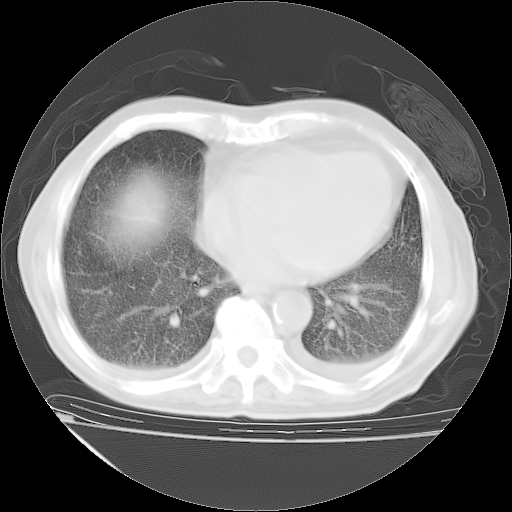

仔细阅读病史资料和CT,我觉得两肺粟粒结核要高度怀疑。

昨天我们影像科主任说由于12天前在齐鲁医院的肺部CT无确切改变,所以不考虑肺结核。

但我们感染病科老主任认为粟粒性肺结核可能性大。

今天带四次肺CT片到市医院,影像科4~5个主任都认为不考虑粟粒性肺结核。主要理由是在3月19日、4月2日、4月27日的CT片没有见到确切异常(肺结核)影像。影像科主任们建议找呼吸内科主任,呼吸内科主任认为首先考虑粟粒性肺结核。

补充下:5月9日胸部CT:似乎已见双下肺胸腔积液了,鉴于目前有下肢水肿,肝功示:白蛋白低,应注意多浆膜腔积液(漏出液可能大?),需注意!

甲强龙80mg/日+抗结核治疗(异烟肼+利福霉素+乙胺丁醇)10天。复查肺部CT。

治疗10天肺部CT